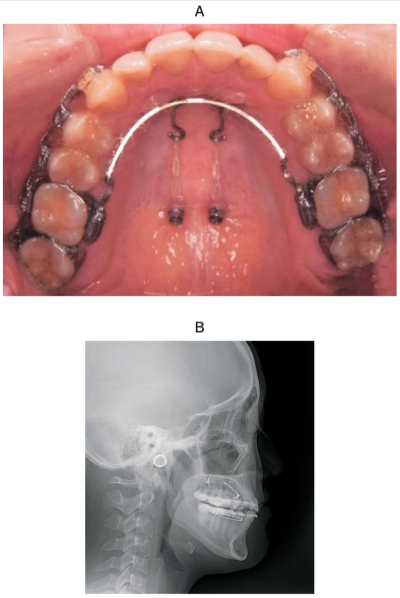

矯正治療中の口腔内写真と側面頭部エックス線規格写真を別に示す。この治療で上顎の歯に起こる変化はどれか。1つ選べ。

a. 犬歯の挺出

b. 側切歯の圧下

c. 前歯の唇側傾斜

d. 第一小臼歯の近心傾斜

e. 第一大臼歯の遠心移動